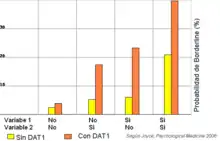

- Transportador de dopamina: un estudio llevado a cabo por Joyce, Kennedy y colaboradores ha encontrado una buena correlación entre el alelo DAT1 y TLP, esta asociación se mantuvo significativa cuando se incluyeron los factores de riesgo, el abuso más negligencia y el temperamento borderline durante la infancia.[15]